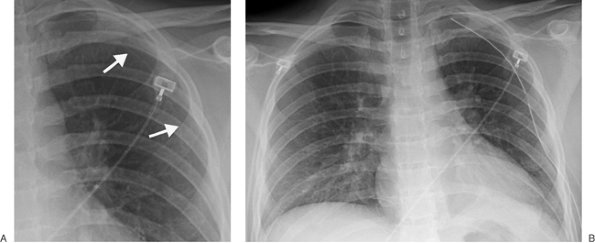

Electrode dislodgment occurs in 3% to 14% of patients (22), generally during the first weeks following insertion. Late displacement is uncommon because of the fibrin sheath that develops between the electrode and the endocardium. Twiddler's syndrome is a rare complication seen in patients with implanted pacemakers or defibrillators; it is a result of the patient either consciously or unconsciously twisting and rotating the implanted device in its pocket, resulting in torsion, dislodgment, and often fracture of the implanted lead (23,24). The diagnosis is confirmed by a chest radiograph, which will reveal a twisted, entangled, and dislodged pacing lead. A small amount of catheter play should be present during systole, but

P.72

none should be present during diastole. If the catheter is short, dislodgment may occur, and the catheter may enter the right atrium, pulmonary artery, SVC, or coronary sinus. If the lead is too long, a bend in the wire may occur, causing lead fracture (Fig. 5-22). A redundant lead may also perforate the myocardium; this complication generally occurs at the time of or within a few days after insertion. The frontal or lateral radiograph will show the catheter tip outside or within 3 mm of the edge of the cardiac silhouette (Fig. 5-23). Perforation can lead to cardiac tamponade or postcardiotomy syndrome. Inflammation and infection can occur within the vein or the generator pocket; the latter occurs in up to 5% of patients (20). Major vein thrombosis and pulmonary embolism are additional complications of pacemaker insertion.